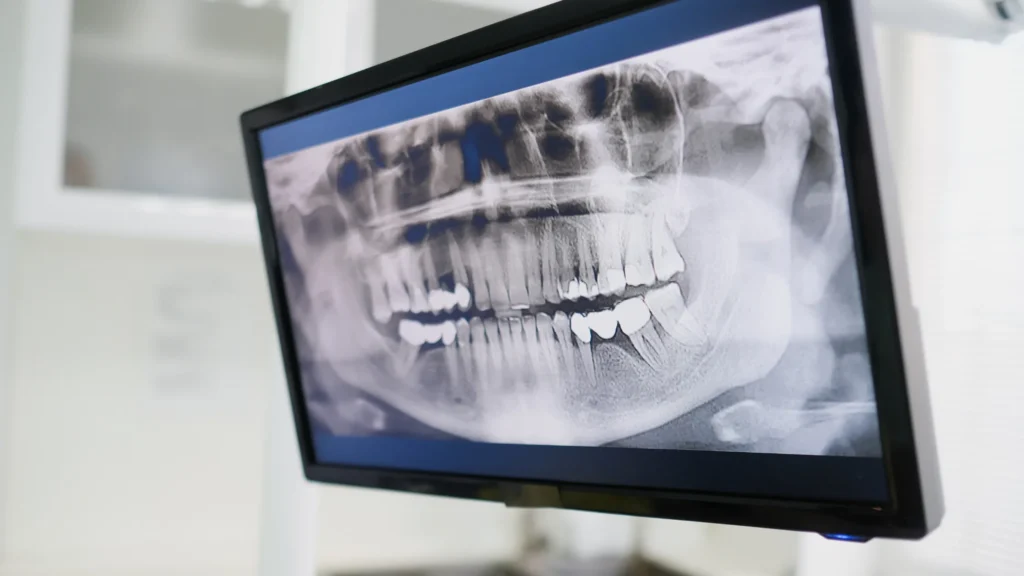

Modern cerrahi teknikler ve gelişmiş görüntüleme yöntemleri sayesinde operasyonlar artık çok daha konforlu, öngörülebilir ve hızlı iyileşme süreçleriyle gerçekleştirilebilir. Doğru müdahale, sadece mevcut sorunu gidermekle kalmaz, aynı zamanda gelecekte oluşabilecek daha büyük fonksiyonel kayıpların da önüne geçebilir.

Çene kemikleri veya ağız içindeki yumuşak dokularda gelişen kist ve tümörler, genellikle rutin diş kontrollerinde tesadüfen saptanır. Bu oluşumlar zamanla çene kemiğini zayıflatarak kırıklara, dişlerin yer değiştirmesine veya ciddi yüz asimetrilerine neden olabilir.